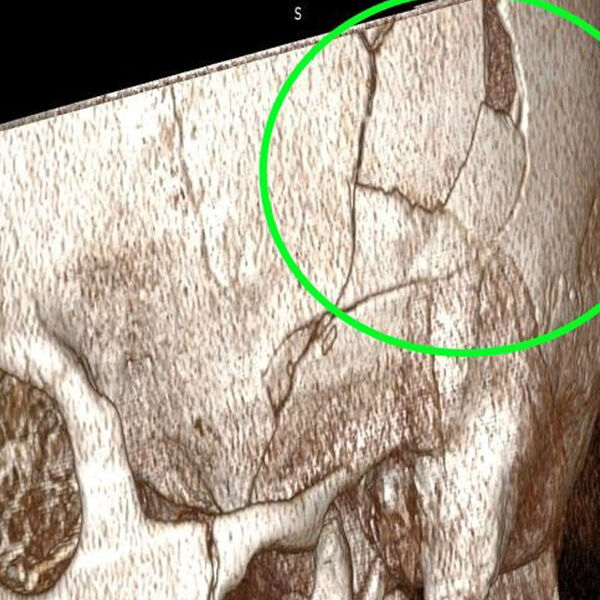

Хирурги Новосибирской ГКБ № 34 спасли мужчину, на голову которого упала коробка передач от«КамАЗа» весом 200 кг. Об этом сообщает Минздрав области.

Пациента доставили в больницу с рабочего места, где он занимался ремонтом «КамАЗа», когда ему на голову упала коробка передач весом 200 кг. Он получил тяжелую травму с повреждением костей и смещением костных фрагментов в полость черепа.

Требовалось срочное хирургическое вмешательство, врачам пришлось заново собирать черепную коробку. Нейрохирургам удалось восстановить целостность черепа без применения имплантов и внешних вставок.